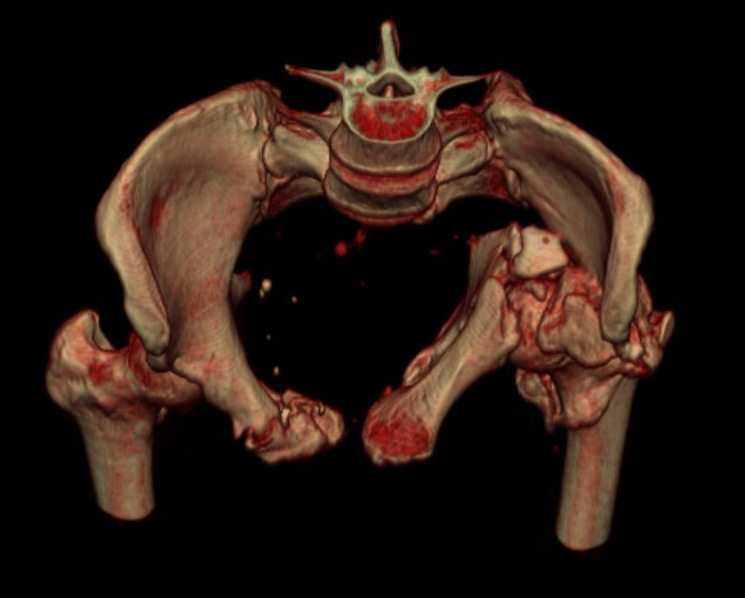

Больная 43 года (промышленный альпинист), 28.07.08 в результате падения с 5 этажа получила политравму:

Перелом свода и основания черепа. Вертикально-нестабильное повреждение таза, осложнённое разрывом мочевого пузыря. Чрезвертельный перелом левого бедра. Перелом правой таранной кости, переломовывих правой кубовидной кости. Тупая травма живота, разрыв печени, ушиб почек. Забрюшинная гематома. В день травмы - лапаротомия, ушивание ран печени. Разрыв мочевого пузыря не диагностирован. Течение болезни осложнилось развитием мочевого затёка и обширной пред- и забрюшинной флегмоны, сформировался свищ мочевого пузыря. 19.8.2008 вскрытие, дренировние флегмоны, ревизия мочевого пузыря, обтурация мочевого свища (свищ закрылся в октябре), 1.10.2008 некрэктомия, пластика по Шеде-Лидскому правой кубовидной кости. По результатам КТ диагностирован рак правой почки (диагностическая находка), 8.10.2008 нефрэктомия справа.

Имеется вертикальное смещение левой половины таза с выраженным отведением крыла (клинически подвижности нет), несросшийся низкий двухколонный перелом левой вертлужной впадины с потерей конгруэнтности, укорочение около5 см, застарелый разрыв лонного сочленения, неправильно сросшиеся переломы обеих ветвей правой лонной кости с укорочением, патологическая подвижность лоно-седалищного фрагмента слева. Правая нижняя конечность неопорна, несмотря на то, что лежа прямую ногу поднимает, ходит на левой ноге (ортопедическая обувь) с костылями, справа тазобедренный ортез. Седалищные нервы работают.Урологи отпустили больную на 6 мес.

Мучаемся мыслями - как все это заставить ходить.Возможно ли первичное протезирование если просто синтезировать лонное сочленение с цементом и ванкомицином?

Если делать большую реконструкцию, то с чего начать? Изрубить крыло и заполнить дефекты? Перерубить боковую массу и попытаться развернуть крыло обратно?